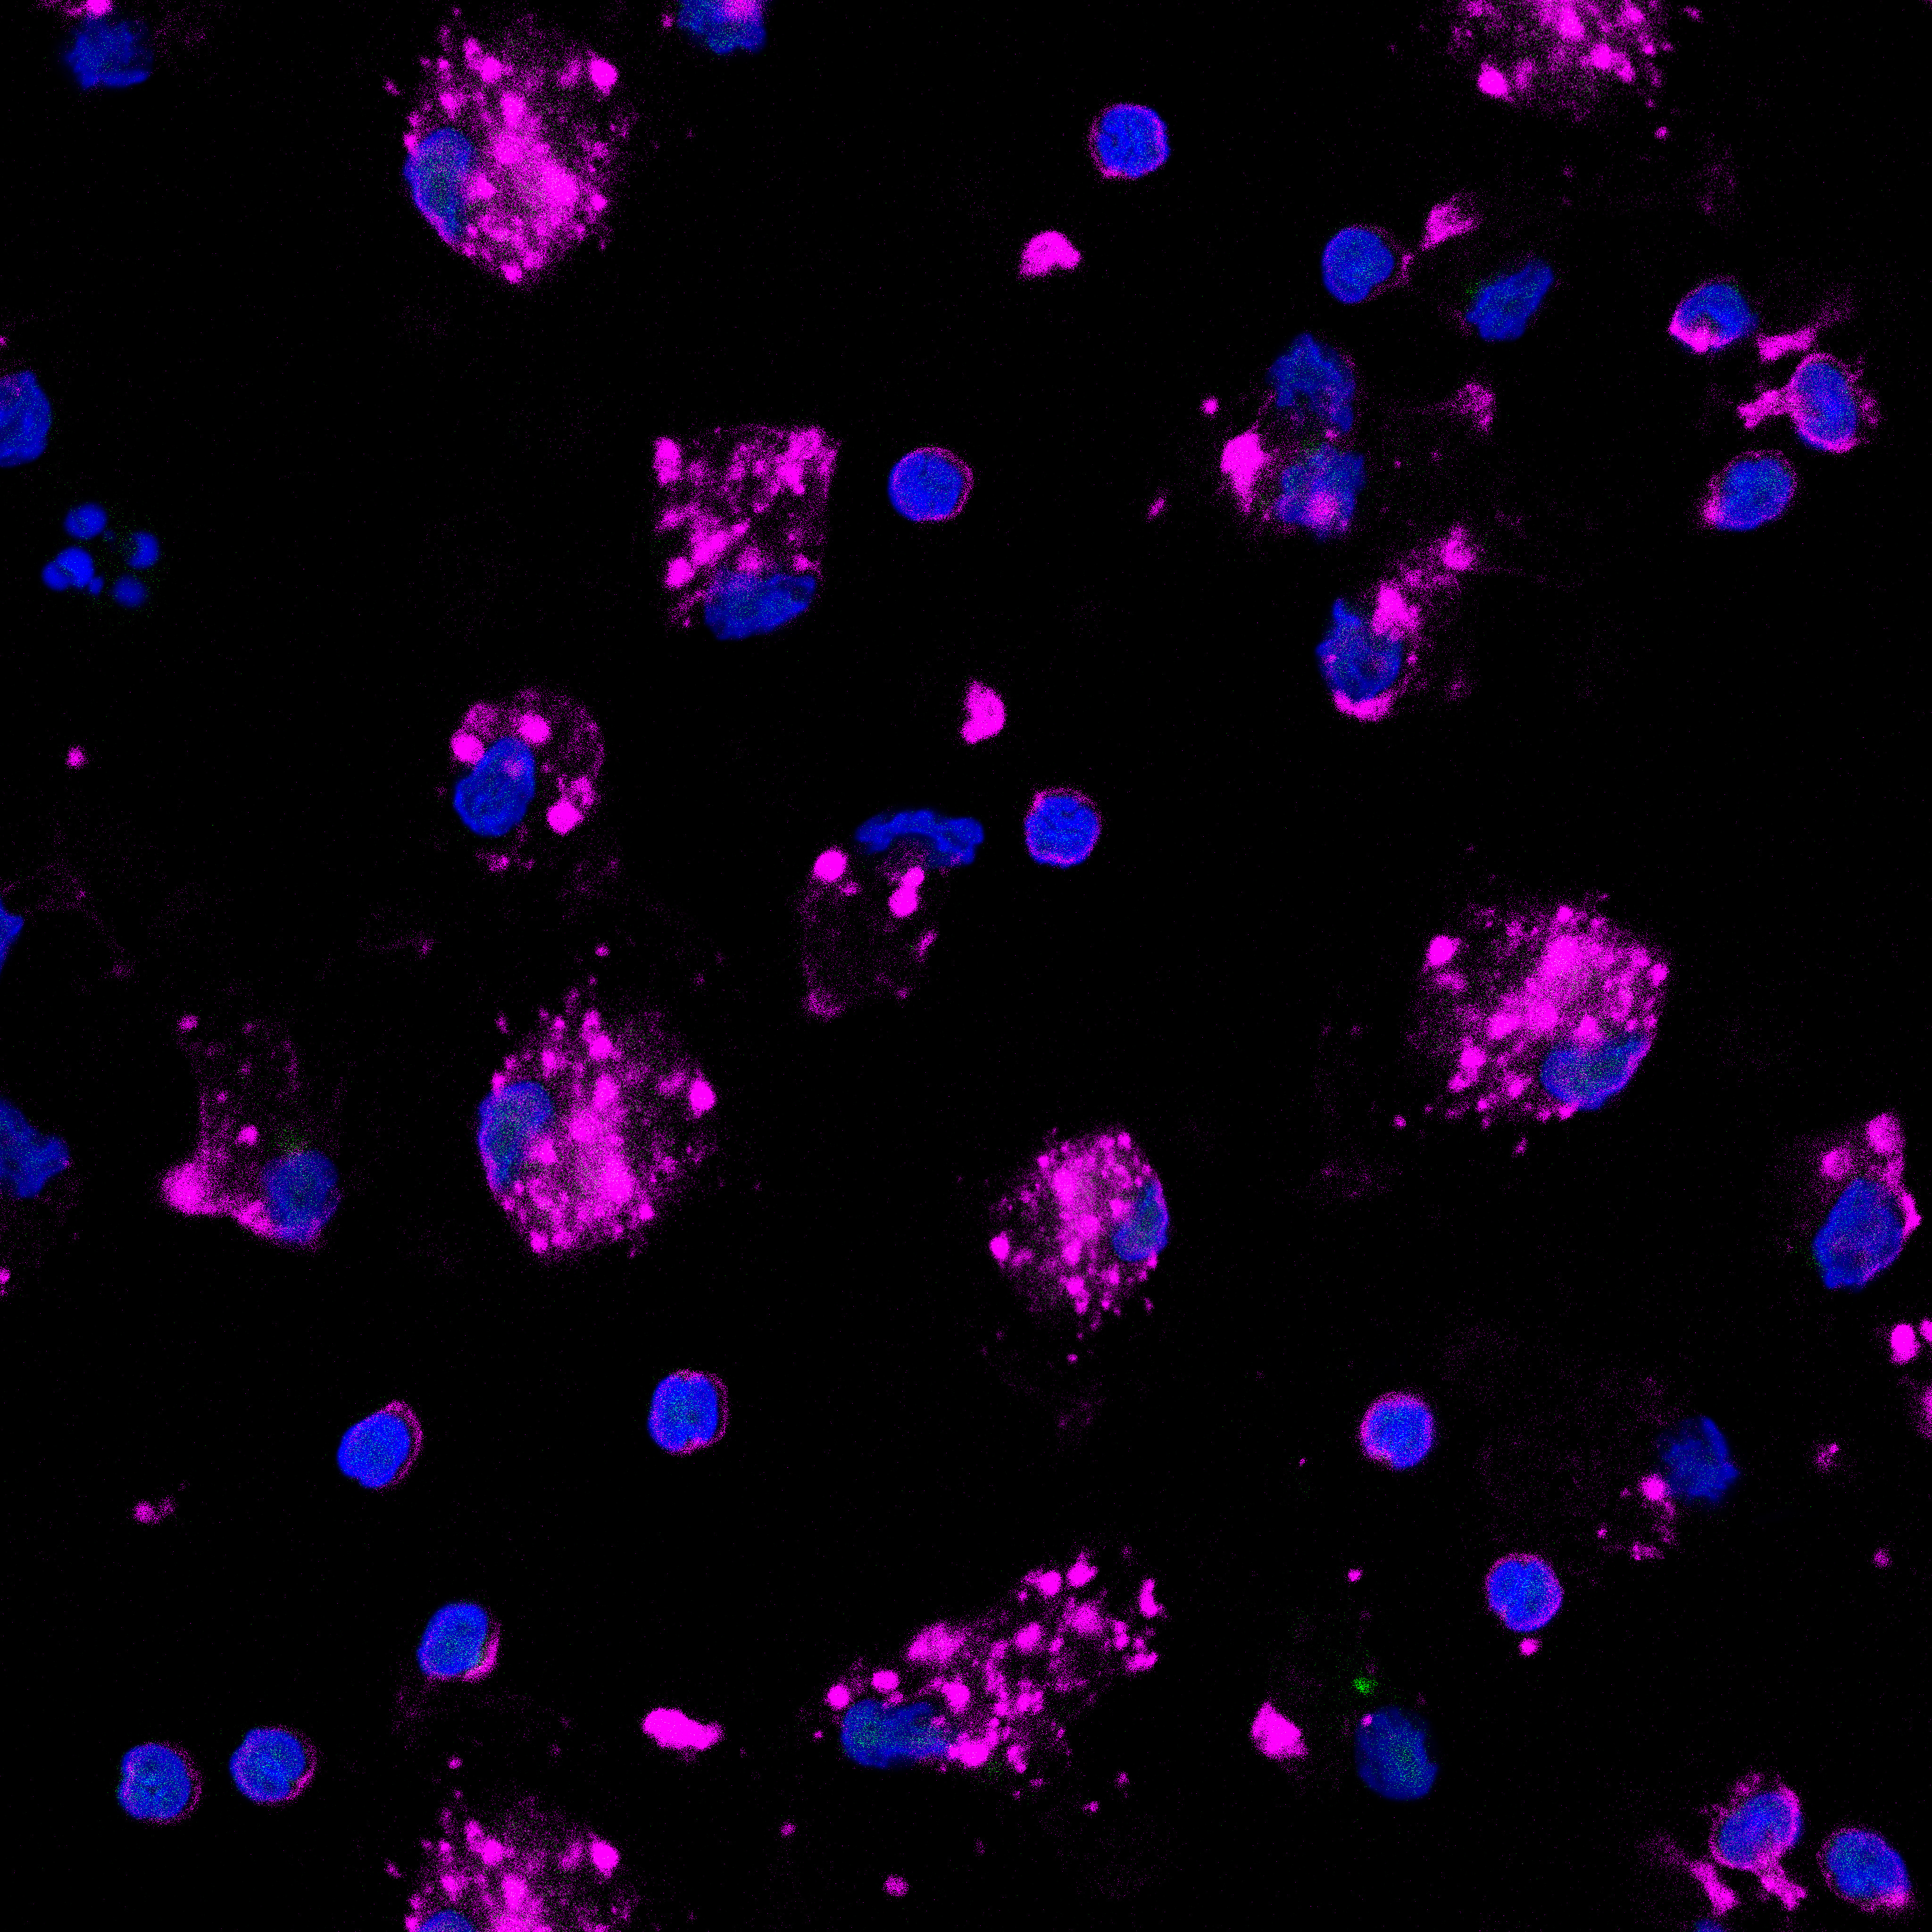

Innowacyjny model finansowania kosztownego leczenia nowotworów złośliwych. Pomysł polega na wykorzystaniu obrazów prawdziwych komórek nowotworowych, przekształceniu ich w dzieła sztuki, a następnie stworzeniu z nich NFT. Pozyskane z akcji środki przeznaczane są na leczenie osób, walczących z przedstawionymi na zdjęciach nowotworami .